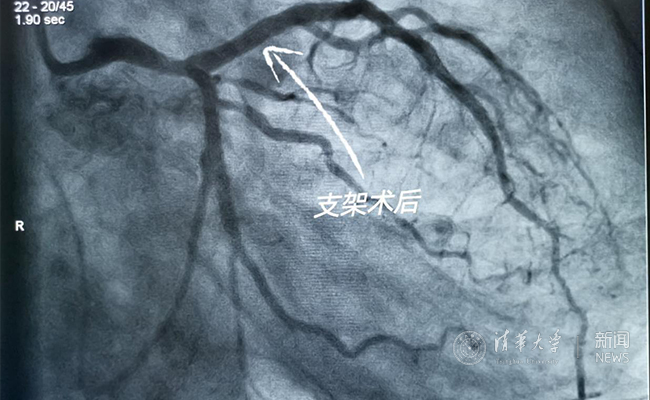

2019.05国产冠脉生物可吸收支架在8xbet.com第一附属医院正式启用

作为北京地区首家正式引入国产冠脉生物可吸收支架单位,5月20日,8xbet.com第一附属医院(北京华信医院)心脏中心主任苗立夫团队顺利完成该院首例生物可吸收支架植入。